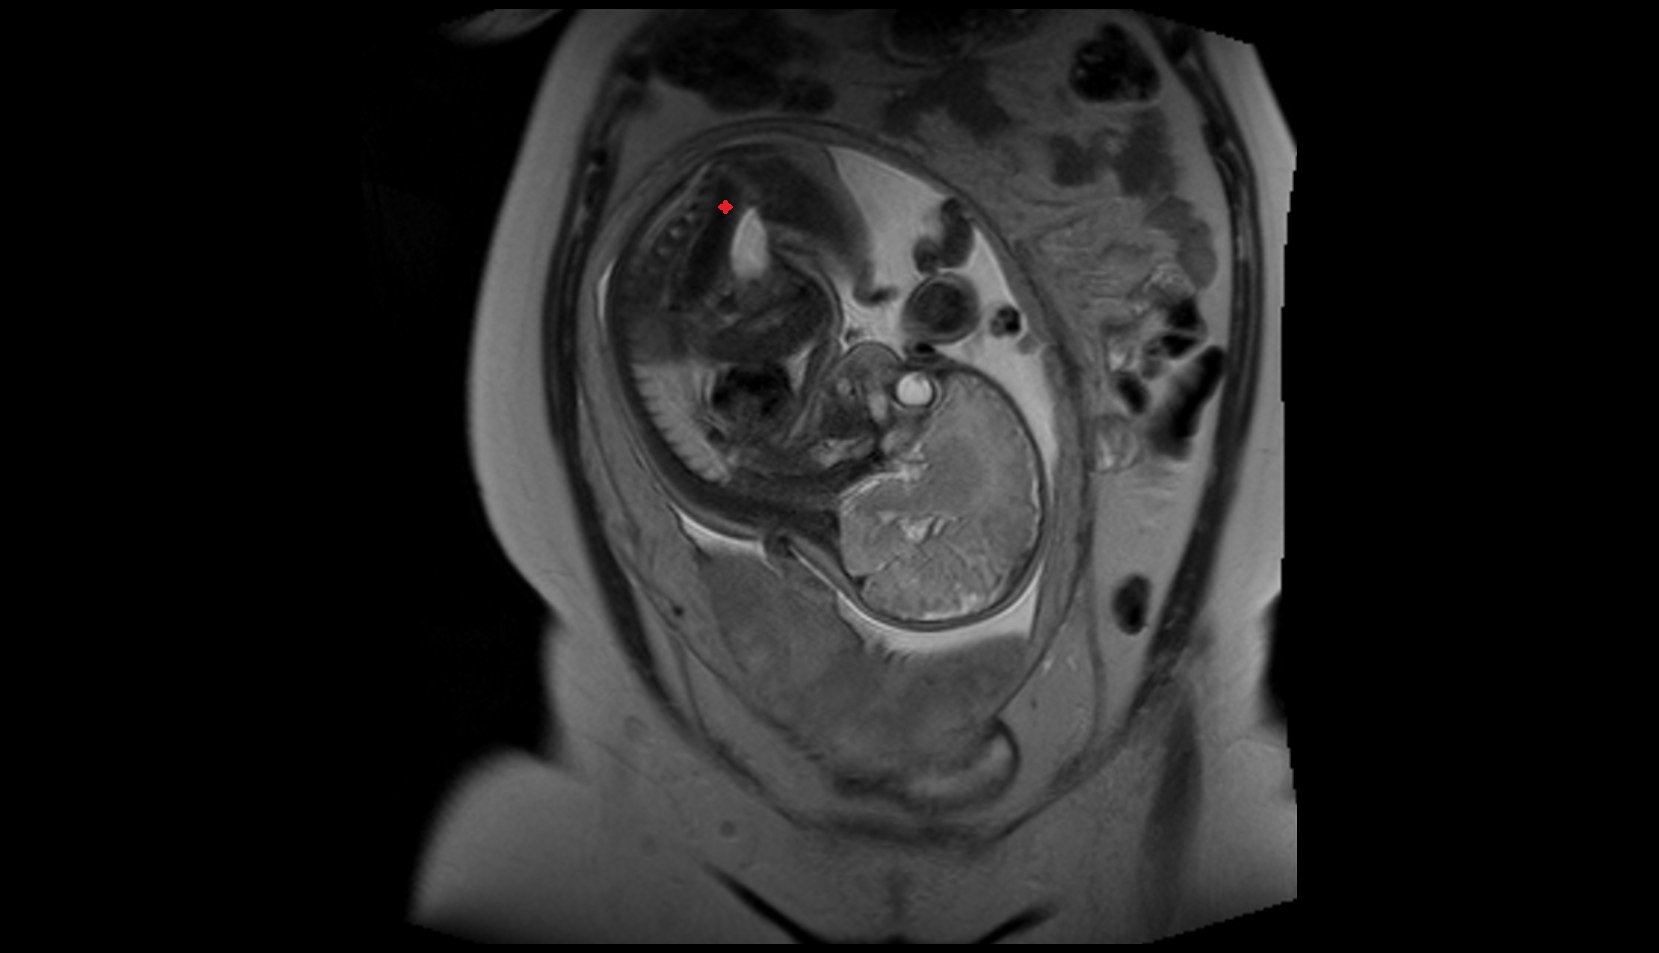

- Placenta

- Uterus (pregnancy)

- Amniotic fluid

- Umbilical cord

- Urinary Bladder in Pregnancy

- Cervix in Pregnancy

- Fetal brain

- Fetal caudate nucleus

- Fetal thalamus

- Fetal pons

- Fetal cerebellum

- Fetal lateral ventricle